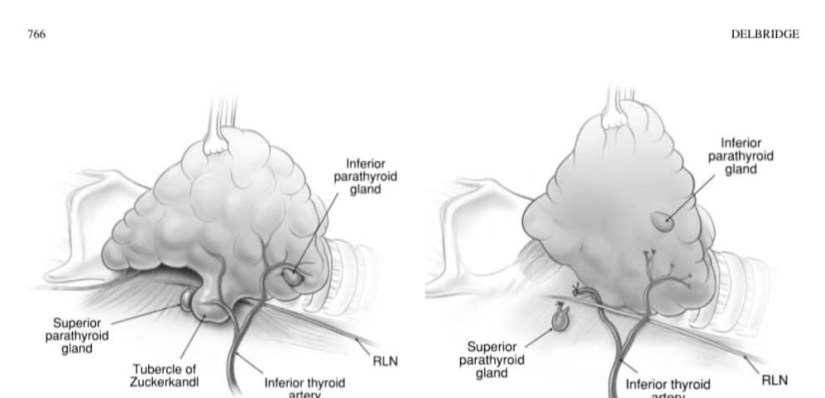

👉Although most authors still favour the approach of selective (‘ready’) parathyroid autotransplantation, routine autotransplantation, a philosophical approach based on the understanding that while parathyroid autotransplantation is very effective, the viability of in situ vascularized parathyroids remains unpredictable with late ischaemia always a possibility.

👉The routine autotransplantation of at least one parathyroid gland during every total thyroidectomy, while unnecessary in most cases, provides insurance in cases where late ischaemia of the remaining glands actually occurs.

👉The parathyroid gland chosen for routine autotransplantation is either one determined to be non-viable on the basis of anatomical location or a failed knife-test, or else the least viable appearing of the remaining in situ glands.

👉Routine autotransplantion will be associated with an increase in the rate of temporary hypocalcaemia in the short term but has, in theory, the potential to reduce permanent hypoparathyroidism to zero.